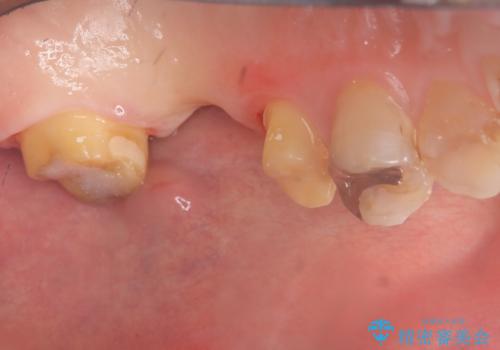

左上7番遠心マージン不適を認め、そこに汚れが停滞していたためやり替えをおすすめし、汚れが付着しずらく審美性に優れたセラミッククラウンブリッジでのやり替えとなりました。

保険適用のメタルインレーを除去したところ、ポンティック部の過度な加圧によって歯肉が強く発赤していたため、一度仮歯に置き換え歯肉の治りを待った後、適切な加圧強さのオールセラミッククラウンブリッジをセットしています。